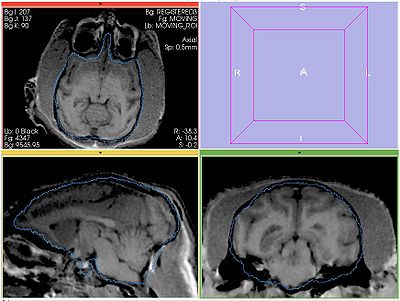

The following screeshots demonstrate good initial alignment of the images with the initial affine transformation, and the outline of ROIs. Also note that FIXED1 and FIXED2 are very similar within ROI.

FIXED1